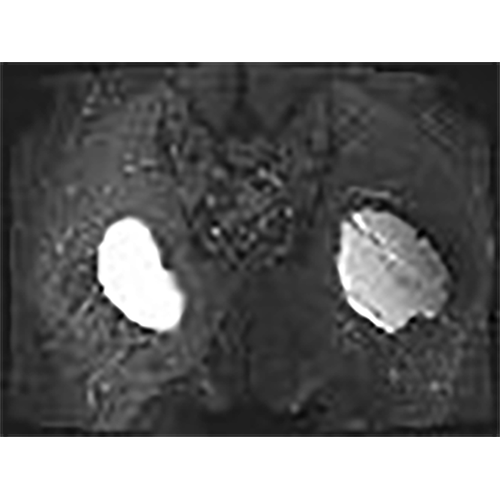

For this case, which will be detailed further, an MRI IS MANDATORY to check the depth as the position of the implants before opting for an indication or an absolute contra indication.

For this case, an MRI IS MANDATORY to check the depth of the implants in case the patient is very thin.

implants are 102x92x34 big,and position between skin and muscle on depth from the skin 16,7mm